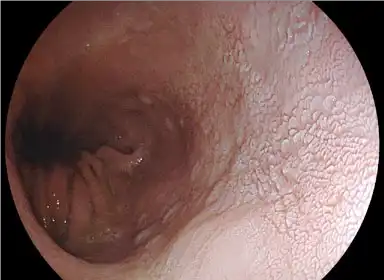

The newly designed high performance optical system enhances close focus observation capability up to 2 mm.

The focus at the edges of an image has been improved,minimizing distortion in observation of a lumen. Through a combination with the megapixel CMOS image sensor, high performance optical system assists various observations ranging from close-up to distant views.